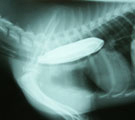

内視鏡下で胃内異物を把持したところ 異物は胸部食道内に滞留してしまった 食道内の異物をマニセプスでしっかり把持した 異物は軟式用テニスボールであった

経過:一般状態良好。一部裂けて穴があいているテニスボールを飲んだという。上腹部X線で胃のほぼ全内腔を占める異物が認められた。椀状につぶれたテニスボールと考えられた。24時間絶食後、全身麻酔下、胃内視鏡検査を施行した。最初は、外径6mmの内視鏡に外付チャネルを設置し、大型の鰐口把持鉗子にてちょうどボールの裂け目を把持して慎重に胃内より牽引し何とか噴門を通過させた。しかし、胸部食道内で大きな抵抗が生じ鉗子が抜けて滞留してしまった。次に、透視および内視鏡観察下に食道内に内視鏡用マニセプスを挿入しそれでしっかり異物を把持し、慎重に牽引して異物回収に成功した。直径6cmの軟式用テニスボールであった。表面は腸液と胃液で変色していた。かなり悪戦苦闘し処置時間は71分だった。経過良好で当日退院した。

コメント:はじめX線を見たときに、「これは90%開腹手術移行だ」と思いましたが、結局なんとか開腹せずに異物をとりだせました。このようなやわらかいものであれば、多少大きくても内視鏡で回収できるかもしれません。